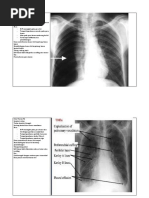

YTH TS :

Hasil pemeriksaan Thorax PA:

- Corakan bronchovascular tampak prominent

- Cor : kesan membesar, aorta dilatasi, elongasi dan kalsifikasi

- Kedua sinus dan diafragma baik

- Tulang-tulang intak

- Tampak bayangan opaq dengan ukuran +/- 3 x 1,5 cm pada regio colli dextra (kalsifikasi pada

thyroid)

Kesan :

- Bronchitis

- Cardiomegaly disertai dilatatio, elongatio et atherosclerosis aorta